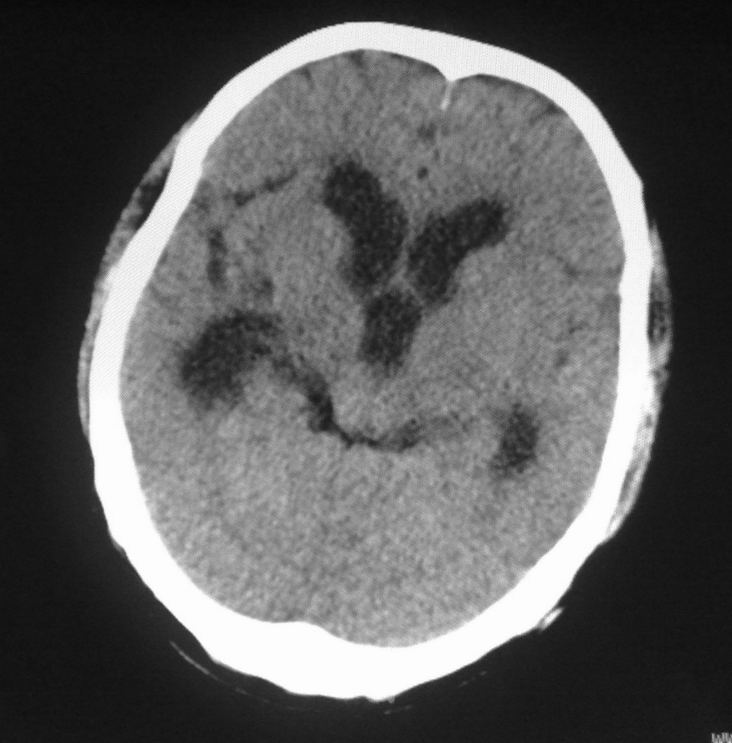

标题: CT24862:男,61岁,发热,有脑出血病史。 [打印本页]

男,61岁,发热,有脑出血病史。

右侧基底节,放射冠软化灶,胼胝体发育不良 脑积水原因待查。

右侧基底节及放射冠软化灶,脑积水,四脑室显示不清,导水管梗阻?建议mri!

梗阻性脑积水,出血后粘连所致

1)右侧基底节区、右侧放射冠及右侧丘脑软化灶。2)脑积水。